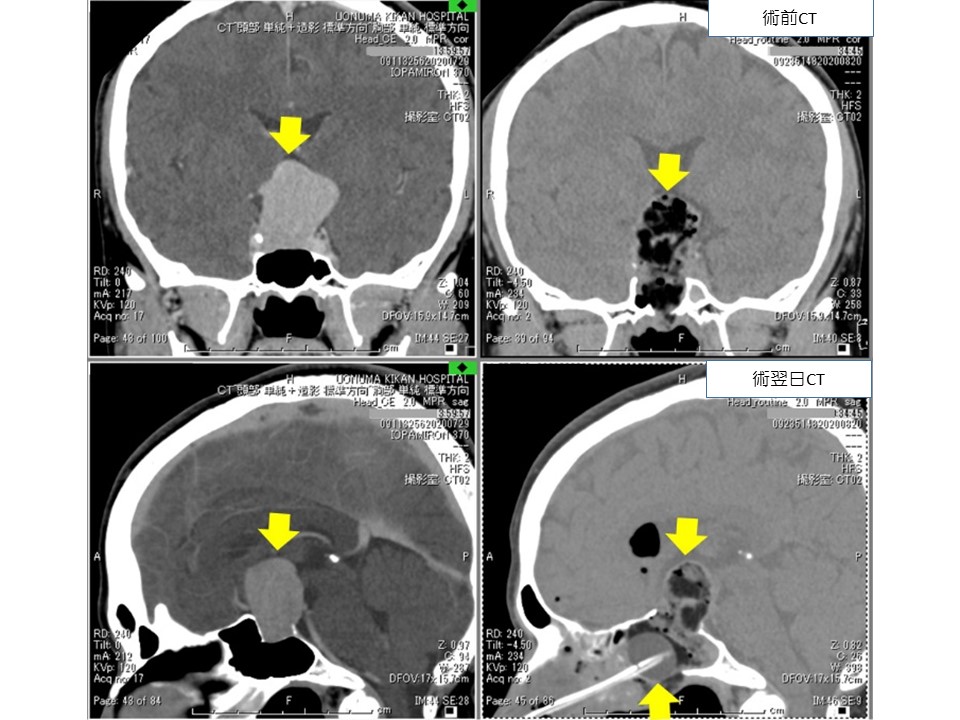

腫瘍が大きくなって下垂体の上にある視交叉(視神経)を圧迫すると視力、視野障害が出現します。視野は両側の外側が見えにくくなる(両耳側半盲)場合が多いです。頭痛もよく見られます。下垂体腺腫を持っている人に突然のひどい頭痛が生じたときには下垂体卒中といって腫瘍の中で出血や梗塞を起こしていることがありますので、すぐに脳神経外科を受診する必要があります。また正常な下垂体組織が障害を受けて下垂体機能低下症(別項参照リンク)をきたすことがあり、1cm以上の非機能性下垂体腺腫の58%の患者さんになんらかのホルモン分泌低下があったという報告があります。

下垂体腺腫に対する手術治療の第一選択は、経鼻的摘出となっており、内視鏡の発達により、従来は開頭手術を要した比較的大きな下垂体腺腫も、内視鏡下に経鼻摘出されます。